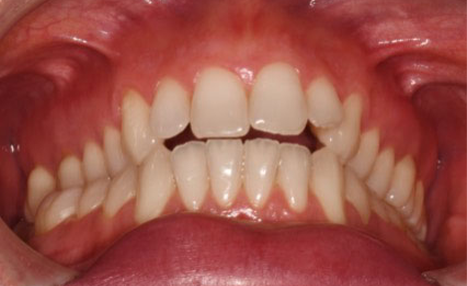

After 16 months of treatment, the transformation was evident:

(Image: 2 years after finishing)